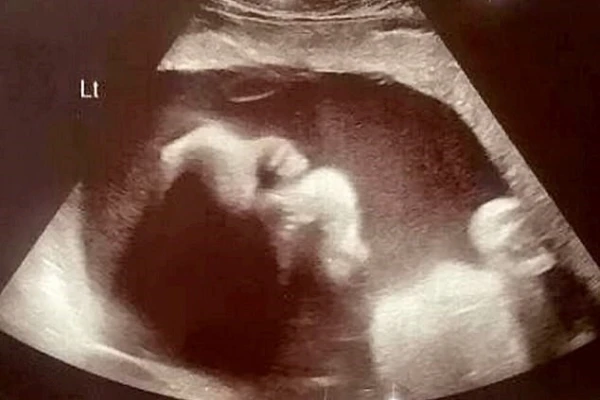

A las 22 semanas de embarazo los doctores diagnosticaron que la bebé tenía espina bífida, condición que afecta a 1.500 embarazos cada año y que, de acuerdo con la Organización Mundial de la Salud (OMS), se trata de "una malformación congénita (llamada comúnmente defecto congénito) por la cual la columna vertebral no se desarrolla normalmente en las primeras semanas del embarazo".

"Fue entonces cuando me dijeron que la bebé tenía espina bífida. Me quebré, era un desastre, y no pude dejar de llorar", recordó. Además le dijeron que su "única opción era abortar", y que si seguía con el embarazo la bebé sufriría graves consecuencias.